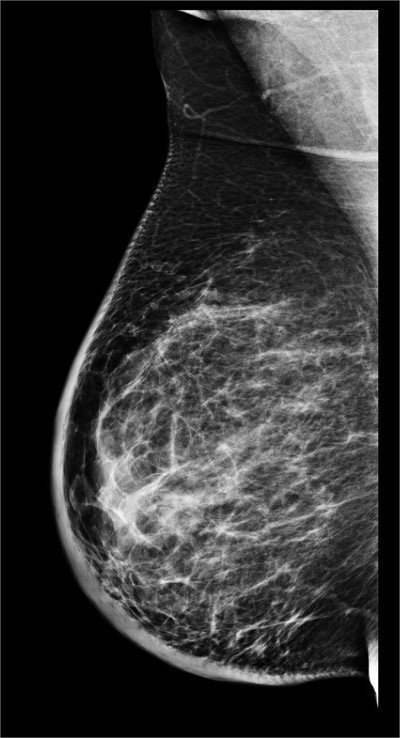

👉The other problem with it is dense breast tissue is white on a mammogram, and breast cancer is white on a mammogram, and so a lot of times the denser tissue can obscure or hide a cancer on the mammogram and making it harder for a radiologist to pick that up.